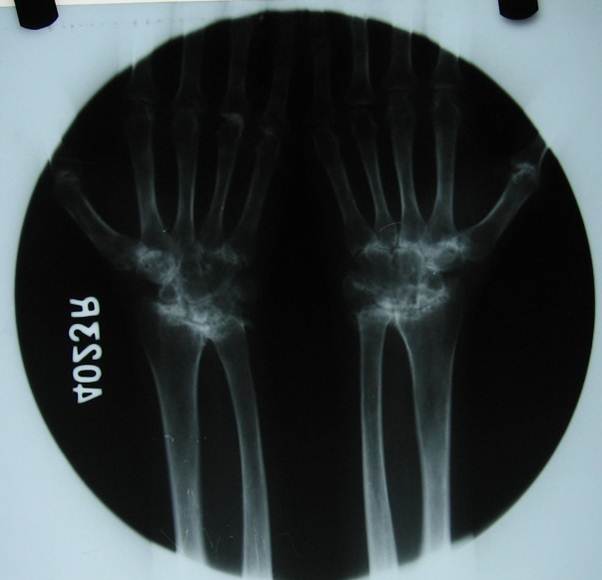

RHEUMATOID ARTHRITIS